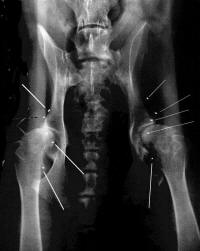

Goldimplantationen bei Hunden

Hierbei werden kleine Goldkügelchen an Akupunkturpunkten dauerhaft implantiert um - ähnlich wie sog. Dauernadeln am Ohr beim Menschen - über eine lange Zeit den Akupunktur-

punkt zu reizen. Das Haupteinsatzgebiet sind Behandlungen im Zusammenhang mit DER Hüftgelenkserkrankung beim Hund: der HD (Hüftgelenks-Dysplasie).

Bei dieser angeborenen Fehlfunktion des Hüftgelenkes kommt es früher oder später zu einer arthrotischen (verknöchernden) Veränderung der Gelenkpfanne und/oder des Oberschenkelkopfes, die aufgrund der dabei auftretenden Schmerzen auch sehr qualvoll für den Hund ist.

Nach entsprechender Diagnoseabsicherung werden unter Vollnarkose mehrer kleine Goldkügelchen mehr oder weniger Gelenksnah eingepflanzt. Die Erfolge dieser Methode sind zum Teil außerordentlich. Wenngleich niemand erwarten sollte, daß er aus seinem 13 jährigen Schäferhund einen 3 jährigen mit dieser Methode machen kann. Auch hier gilt natürlich, daß eine frühzeitige Diagnose und Therapie schon die Entstehung dieser Knochen-

zubildungen erheblich verzögern, wenn nicht sogar verhindern kann.

Goldimplantationen bei Hunden |